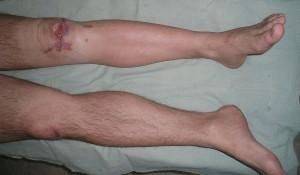

Поражение голени захватывает процесс в большеберцовой кости, что протекает с резкими нарушениями функции конечности:

- острейшая боль;

- отек голени;

- невозможность ходить;

- нарастание интоксикации;

- гектическая лихорадка.

При воспалении только малой берцовой кости сила болезненных ощущений снижается. Однако оперативный доступ к ней затруднен, а при присоединившемся нарушении кровоснабжения в нижних конечностях болезнь часто затягивается.